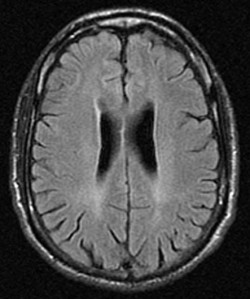

As shown by the MRI scan above, there is general cortical atrophy along with damage to the frontal, parietal and cingulated regions of the brain, with the majority of the damage occurring in the frontal lobe.